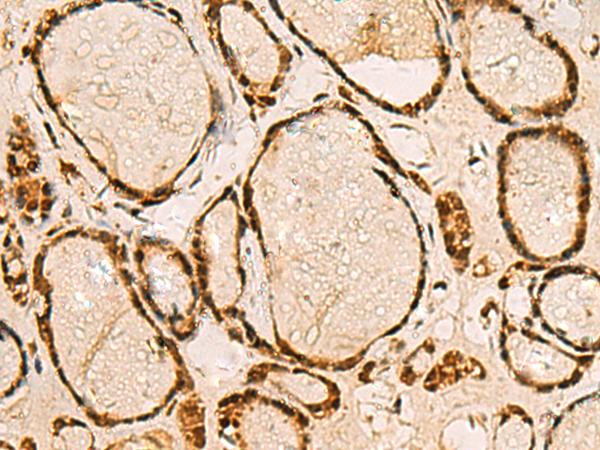

分类: 科研抗体货号: P03348别名: CSS应用: WB,IHC反应种属: Human, Mouse, Rat